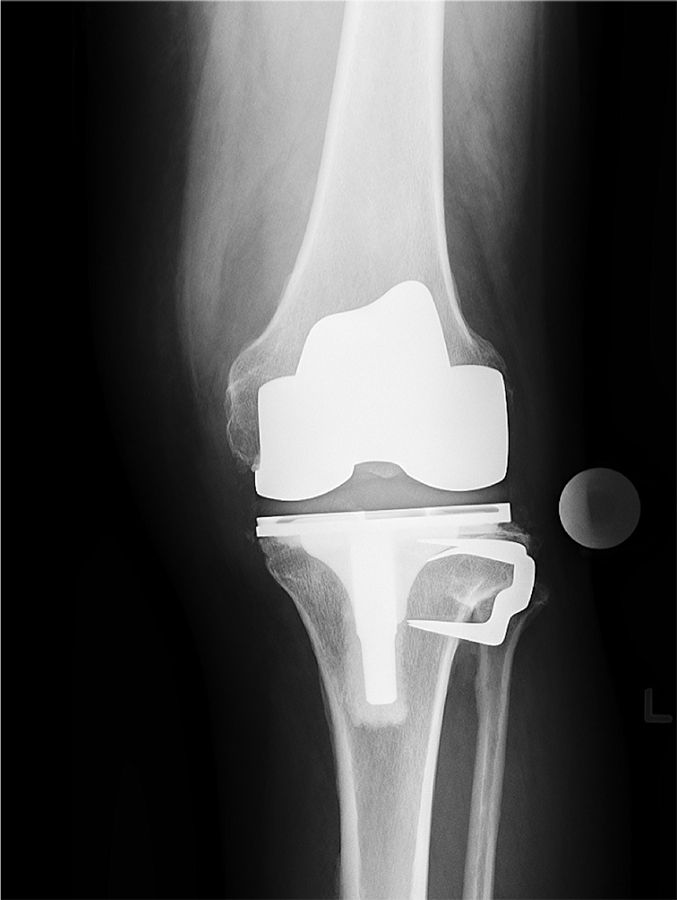

The risk of vascular injury and the difficulty of exposure is less when the femur is subluxated anterior, however, this situation is not without difficulties itself. Usually anterior subluxation of the femur on the tibia results in a significant flexion contracture and significant distal femur resection is needed to allow full extension of the knee and balance flexion and extension space. Based on my personal experience I strongly favor a hinge implant for posttraumatic anterior or posterior dislocations of the femur (Figure 5a, b, c, d).

My rational for this implant choice is that in severe anterior dislocation of the femur, often, the insertion of the collateral ligaments gets compromised when additional distal femur resection is needed to allow full extension. In addition, it is difficult to achieve reliable postoperative range of motion when encountering a knee subluxation in the presence of preoperative stiffness (less than 80 degrees arc of motion). Since the combination of a traumatic dislocation is seldom associated with an addition extraarticular deformity stemmed hinge implants can usually be used without problems.

4. I favor hinge implants for patients with anterior and posterior knee dislocations and an overall arc of motion of less than 80 degrees.